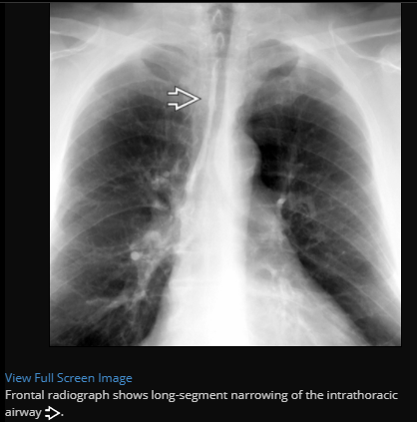

Saber sheath trachea, pathognomonic for COPD

Best diagnostic clue: Side-to-side narrowing of intrathoracic trachea